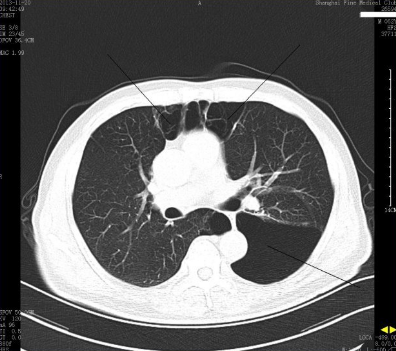

长期吸烟或从事特种行业的人到医院体检后有的会提示有肺大泡。

肺大泡是肺大泡指的就是我们的肺部,由于各种原因导致的肺泡腔内的压力增大,肺泡壁破裂相互融合,在肺组织内形成的一种囊腔。

但我在临床上会碰到一种十分类似肺大泡的肺癌,这是一种最容易误诊和漏诊的肺癌类型。

临床工作中从形态学上把这种肺癌叫做囊腔型肺癌。

囊腔型肺癌的囊腔一般壁比较厚的,且不均匀,生长缓慢,随访过程中空腔可增大、缩小或不变。

囊腔型肺癌占肺癌患者中的比例2%左右,漏诊率高达22%。